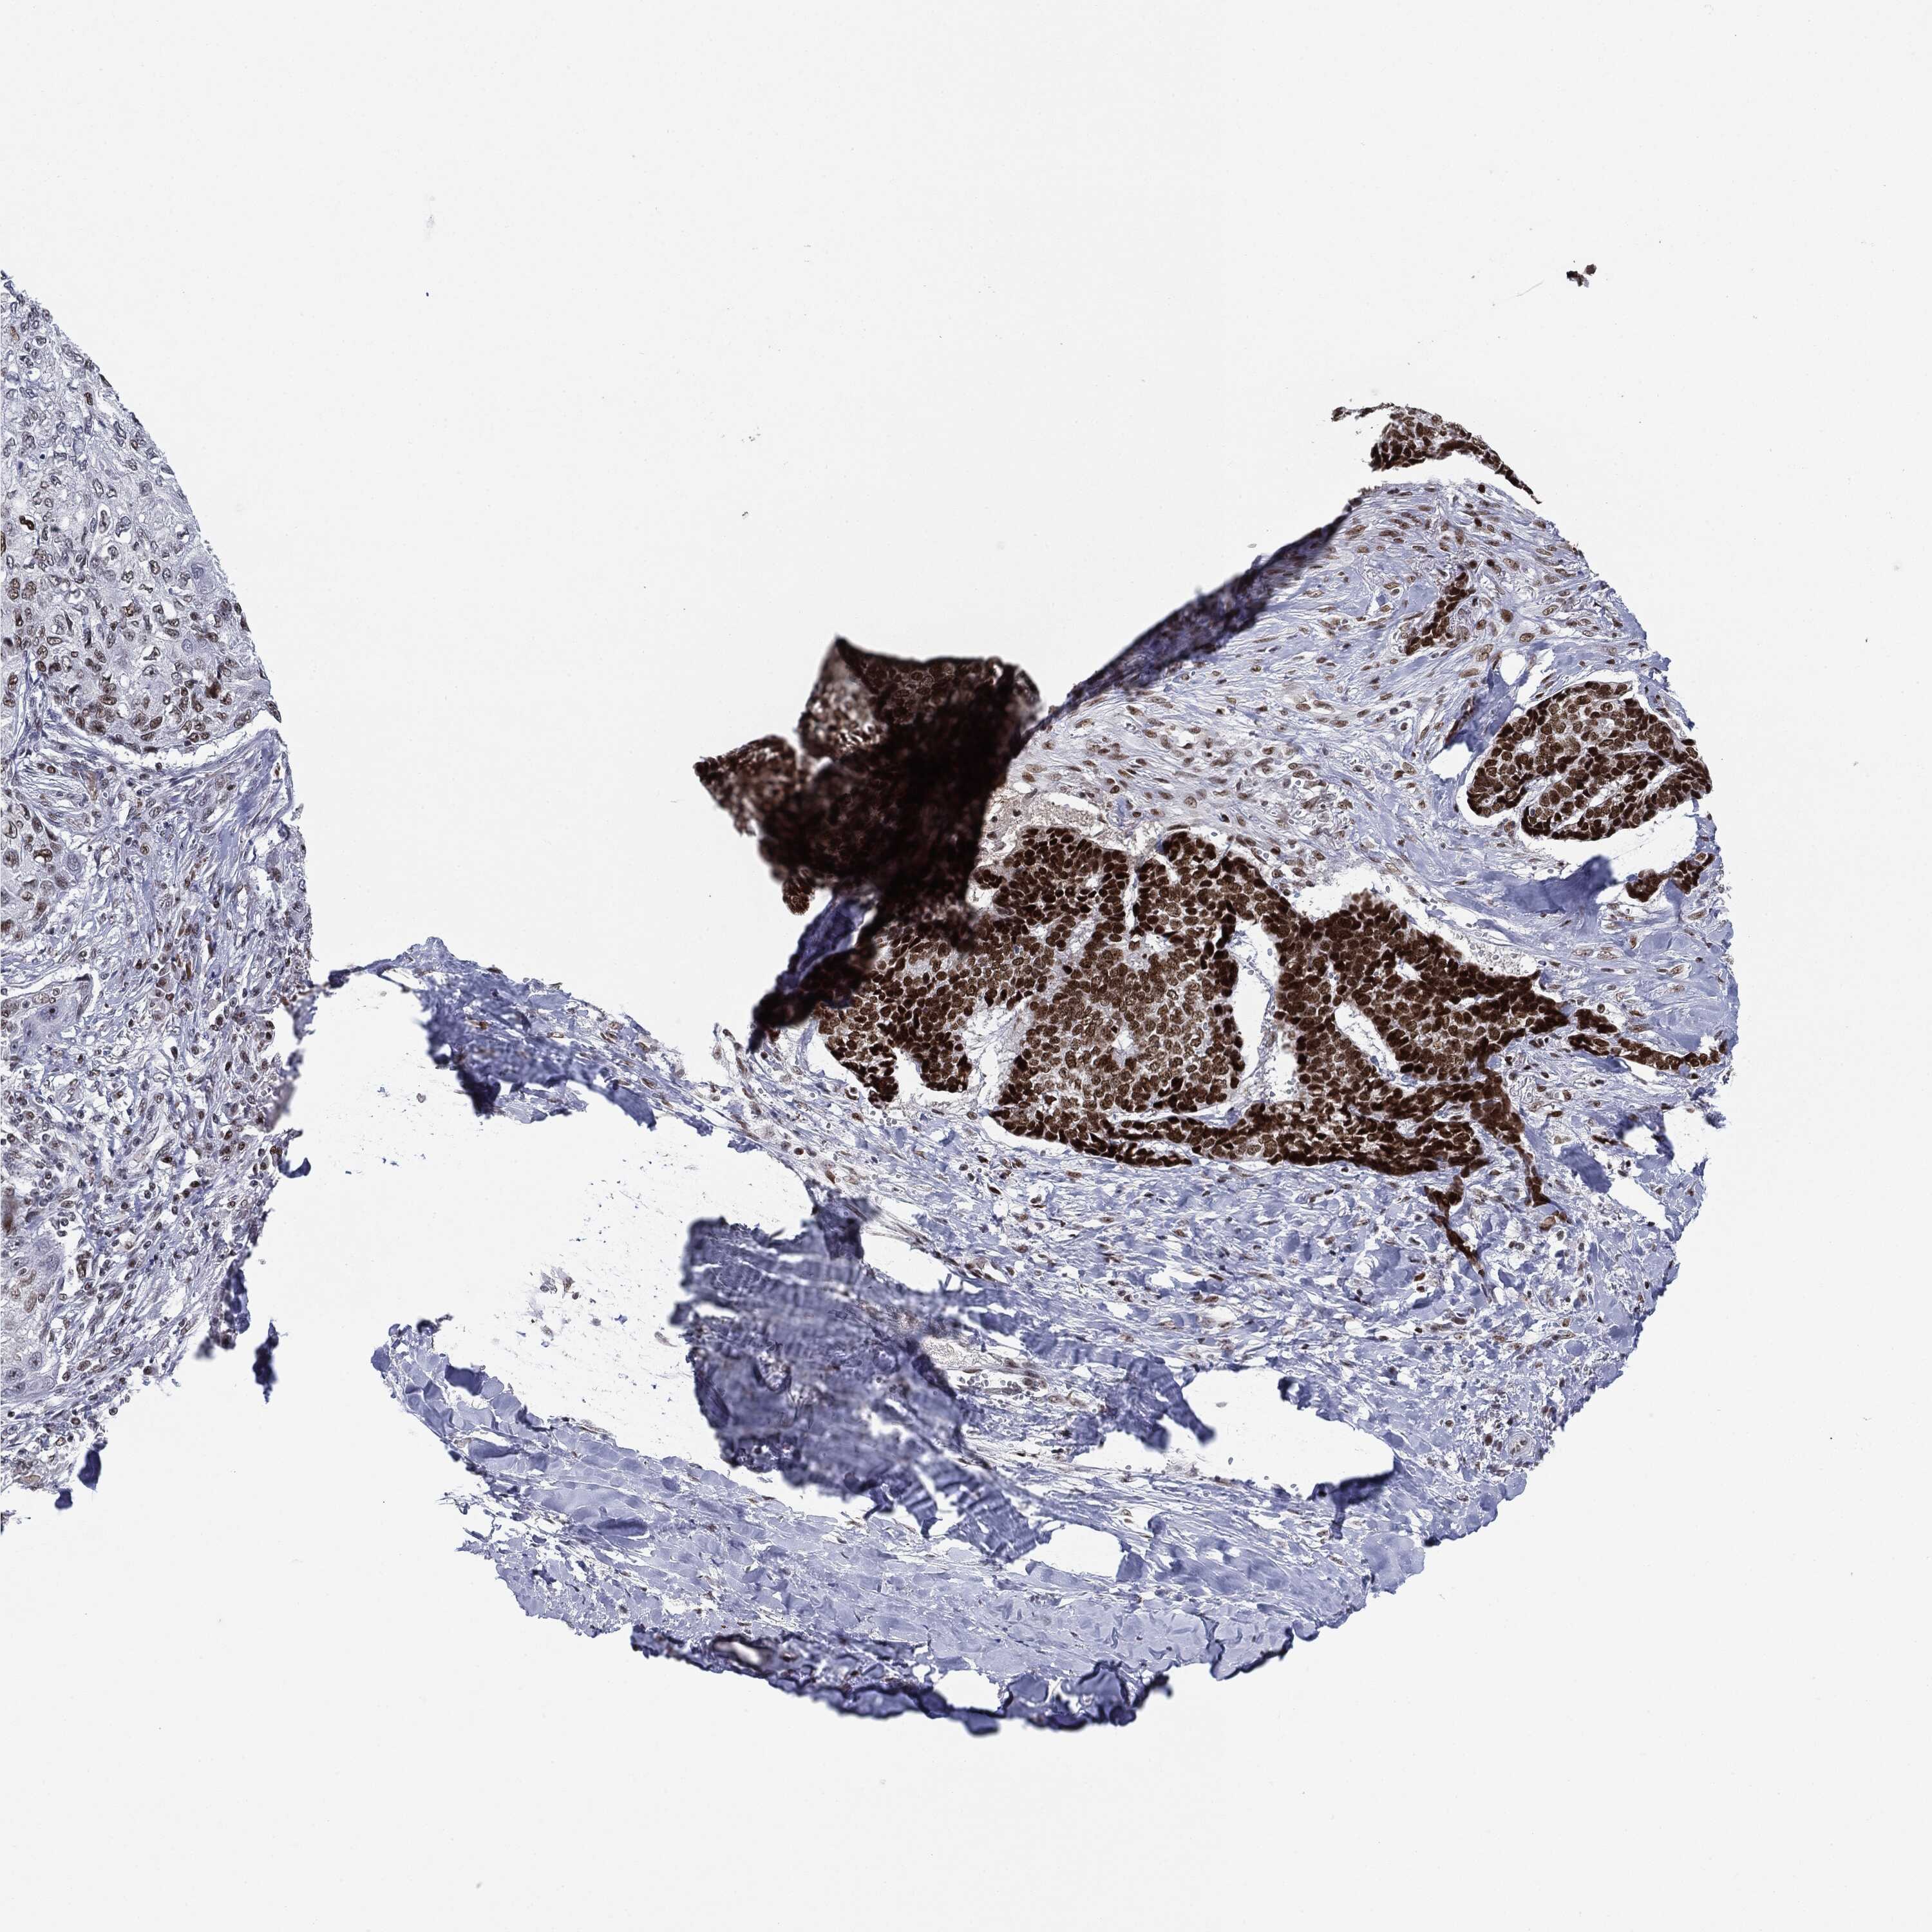

SKIN CANCER - Protein expressioni

A mouse-over function shows sample information and annotation data. Click on an image to view it in a full screen mode. Samples can be filtered based on level of antibody staining by selecting one or several of the following categories: high, medium, low and not detected. The assay and annotation is described here.

Antibody stainingi

Antibody staining in the annotated cell types in the current human tissue is reported as not detected, low, medium, or high, based on conventional immunohistochemistry profiling in selected tissues. This score is based on the combination of the staining intensity and fraction of stained cells.

Each image is clickable and will lead to virtual microscopy that enables deeper exploration of all samples and also displays staining intensity scores, fraction scores and subcellular localization as well as patient and tissue information for each sample.

Antibody CAB080116

Staining

High

Intensity

Strong

Quantity

>75%

Location

Nuclear

Squamous cell carcinoma, NOS

Squamous cell carcinoma, metastatic, NOS